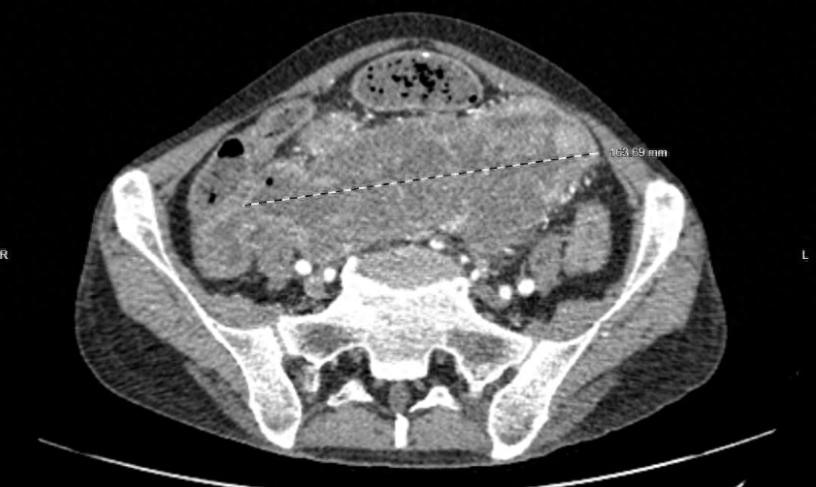

在仔细检查评估后,尹晖明主任发现,胡先生体内肿瘤十分巨大,累及盆腔内大部分脏器,乙状结肠、部分回肠、回盲部、升结肠、膀胱、右侧盆壁等部位,毗邻腹盆腔重要脏器及重大血管主干及分支,合并肠梗阻、中度贫血、低蛋白血症、严重营养不良等多种并发症,手术难度和危险程度相当高。

“患者的肿瘤太大,病变侵及多个器官,与腹膜后大血管分界欠清,如何根治性的切除这么大的肿瘤且尽量保护周围血管、神经,并保证患者远期预后,是手术的难度所在”,尹晖明主任表示。

▲CT下胡先生体内的巨大肿瘤

为确保将手术风险降到最低,经过多学科评估以及周密的围术期管理方案,在患者贫血及低蛋白血症等得到有效纠正的前提下,8月23日,医院普通外科主任尹晖明带领团队医生副主任医师谢承志、主治医师唐曙光、住院医师邓浩进行了“乙状结肠恶性肿瘤根治术+腹腔镜下全盆腔脏器切除手术”,术中见盆腔肿瘤大小约20*16*15cm,如术前所预计的一样,乙状结肠肿瘤累及部分回肠、回盲部、膀胱、右侧盆壁,术中行乙状结肠癌根治+全盆腔淋巴结清扫+部分回肠升结肠切除+膀胱全切。将降结肠与直肠残端吻合,保住患者的排便功能,明显提升了患者术后的生活质量。